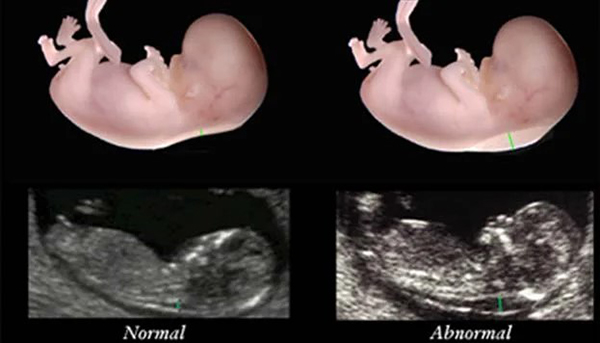

Ở thai nhi, khoảng da sau gáy có chứa dịch. Vùng da này có độ mờ nhìn thấy được thông qua siêu âm. Khoảng mờ có thể hướng lên về phía xương sọ và phía dưới kéo dài đến vùng lưng của thai nhi. Đây là vùng quan trọng phản ánh tình trạng sức khoẻ thai nhi khi đến một giai đoạn nhất định, khoảng từ tuần 10-14.

Thai nhi khoẻ mạnh có lớp da gáy biểu hiện độ mờ thấy rõ. Tuy nhiên ở những thai nhi đang hoặc có nguy cơ cao mắc phải hội chứng Down, vùng da gáy có độ mờ cao hơn hẳn. Nguyên nhân là vì lớp dịch dưới da ở thai nhi tăng lên. Ngoài hội chứng Down, những bệnh liên quan đến rối loạn nhiễm sắc thể cũng sẽ biểu hiện thông qua độ mờ da gáy.